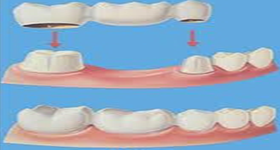

Crowns (caps) are used to cover teeth that are weakened by decay, severely damaged, chipped or discolored. Crowns are frequently on teeth required after root canal therapy on molars on premolars to protect them from fracture. The tooth is shaped to support the crown. Crowns can be metallic or metal-free. The advantage of metal free crowns, such as Zirconia and E.max, are the masking of the gray hue on the gum line caused by the silver colored metal. In certain situations, computer technology is also utilized to fabricate these metal free restorations at Amrapali Dental Clinic. Contact us to find out if you are a candidate for metal-free restorations. While implant dentistry has decreased the need for bridges, we at Amrapali Dental Clinic still frequently use the classical bridge to replace a missing tooth. Two or more teeth on either side of a missing tooth are shaped to receive a bridge. Bridges can also be metallic or metal free.